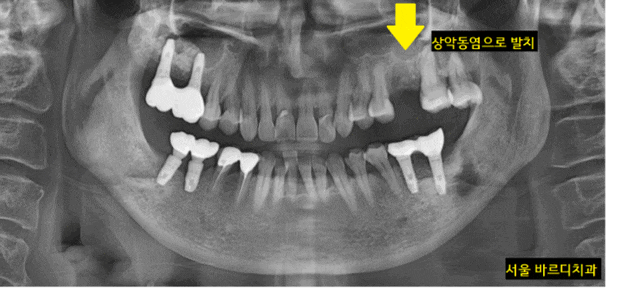

미사역 임플란트 상악동염으로 치아를 발치한 사연

오늘 소개해 드릴 환자분은 치아로부터 상악동 염증이 발생한 분입니다.

원인 파악을 위하여 전체 x-ray 촬영

역시나 왼쪽 윗니 치아에 문제가 있었습니다.